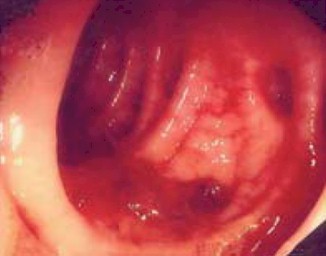

Para localizar inicialmente la fuente de la hemorragia diverticular, se utilizan diversas modalidades diagnósticas. La colonoscopia es un procedimiento en el que se inserta un tubo flexible con una cámara en el extremo a través del recto para examinar el colon. Este método permite la visualización directa de los divertículos y la identificación del sitio de la hemorragia. Alternativamente, la angiografía por tomografía computarizada de planos múltiples (TC) puede ofrecer imágenes detalladas de los vasos sanguíneos, ayudando a localizar el origen del sangrado. También se puede emplear la gammagrafía con eritrocitos marcados, una técnica que utiliza trazadores radiactivos para detectar la ubicación de la hemorragia.

Estos enfoques diagnósticos son cruciales para determinar la causa de la hemorragia, orientar el tratamiento y brindar una atención adecuada. La elección de la técnica diagnóstica dependerá de la situación clínica específica y la disponibilidad de recursos.